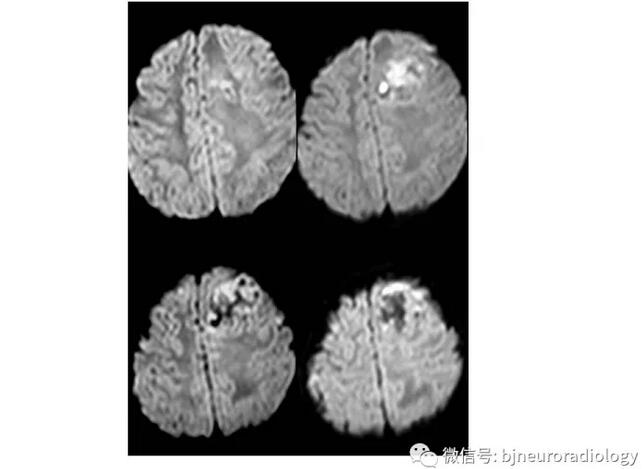

少数室管膜瘤会发生在皮层,表现与脑外肿瘤相似,也可累及颅骨,需与脑外鉴别。室管膜瘤通常发生于儿童,在皮层表现为明显强化的团块,病变内可以囊变坏死。本病例提示儿童皮层肿瘤应注意考虑室管膜瘤,特便是在脑内脑外病变难以确定的时候,应考虑本病变。